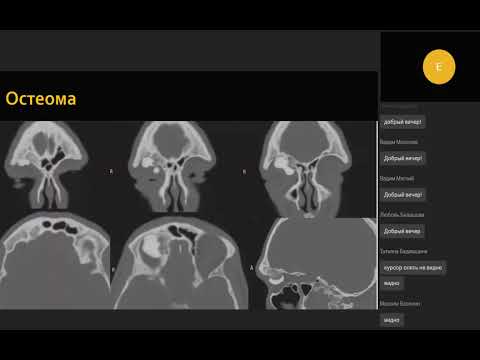

Компьютерная томография при опухолях придаточных пазух носа